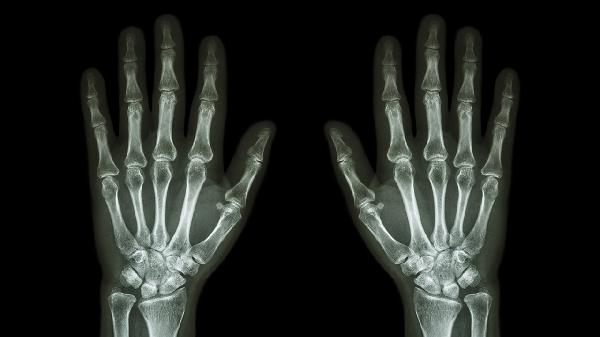

中老年人群多见拇指腕掌关节骨关节炎,与软骨磨损相关。典型症状为关节粗大变形和持物疼痛,X线可见骨赘形成。可遵医嘱使用硫酸氨基葡萄糖胶囊修复软骨,配合关节腔内注射玻璃酸钠。注意避免提重物,使用宽柄工具减轻负荷。